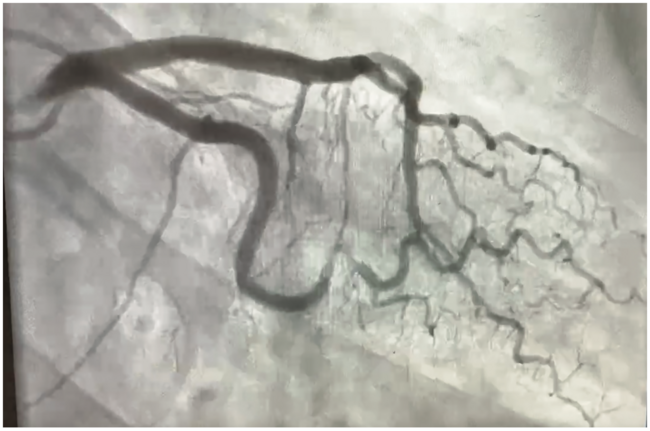

A 54-year-old female presented with acute onset of typical substernal chest pain and was hemodynamically stable. A coronary angiogram (Figure 1/Videos 1-2) showed spontaneous coronary artery dissection (SCAD) type 2a in first obtuse marginal artery. The patient was managed conservatively with medical management and close monitoring with resolution of symptoms.

The majority of SCADs heal spontaneously as seen on follow-up angiogram after over a month and as such, this justifies conservative management in these patients who do not have active ischemia or total occlusion, and if there is TIMI II or III flow.

While SCAD generally heals spontaneously, acute extension in a few cases may be seen early before eventual healing. Coronary computed tomography may have a role for the evaluation of SCAD healing at 6 weeks. Beta-blocker therapy and the avoidance of triggers can help to reduce any recurrence.